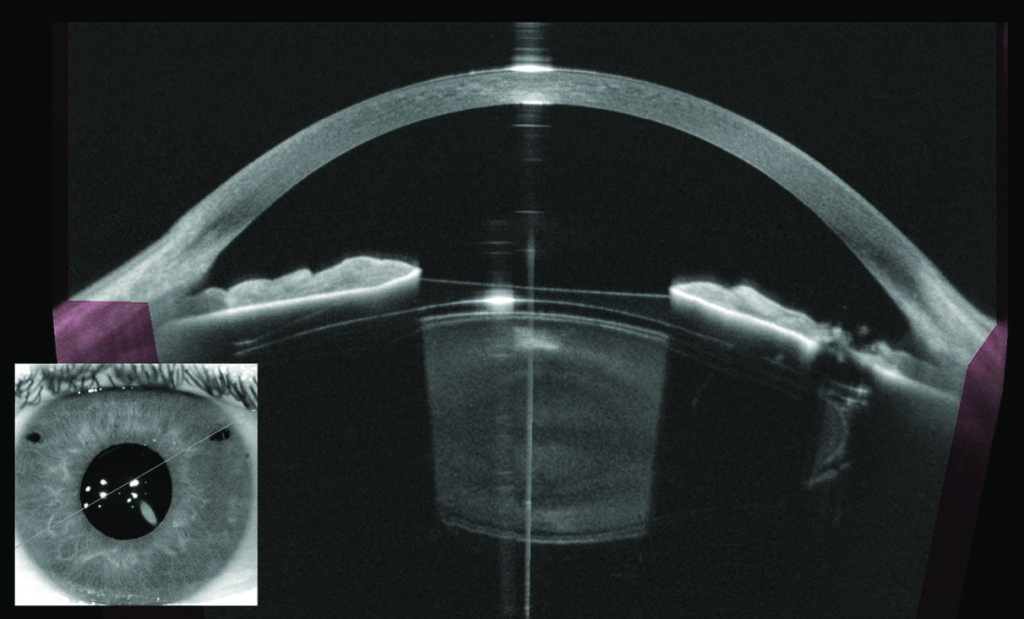

What is an anterior segment photograph?

During your eye clinic appointment you may need the outside of your eye (anterior segment) photographing to keep an accurate record of your eye condition.

This can help the doctor to diagnose, plan treatment and record your condition.